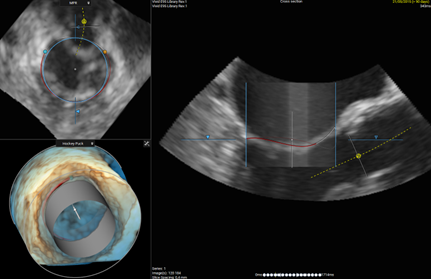

Besides preplanning, screening of patients becomes important given the increasing number of patients that could benefit from mitral valve replacement. The unique 3mensio Mitral 3D TEE workflow offers analysis of the 3D TEE dataset of the mitral valve, can quantify the mitral valve annulus, leaflets and neoLVOT. 3D TEE pre-planning could also serve as a substitute to CT if the latter is contraindicated. 3mensio Mitral 3D TEE is a promising tool for screening purposes. One interesting (future) application of the software lies in preplanning of valve-in-valve cases.

Bringing both 3D TEE and CT worlds together is straightforward with 3mensio. The registration workflow facilitates that the virtual implant of the valve is in the same position on my 3D TEE screening as it is on the CT scan that I use for preplanning."